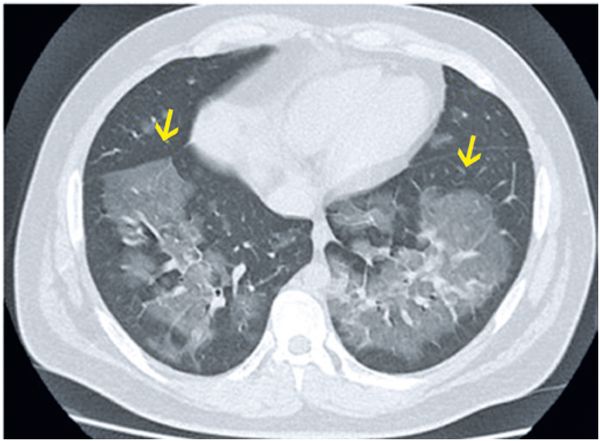

- Характерные изменения на рентгенограмме или КТ (симптом двустороннего матового стекла на компьютерной томографии).

Симптом двустороннего матового стекла на КТ [18]